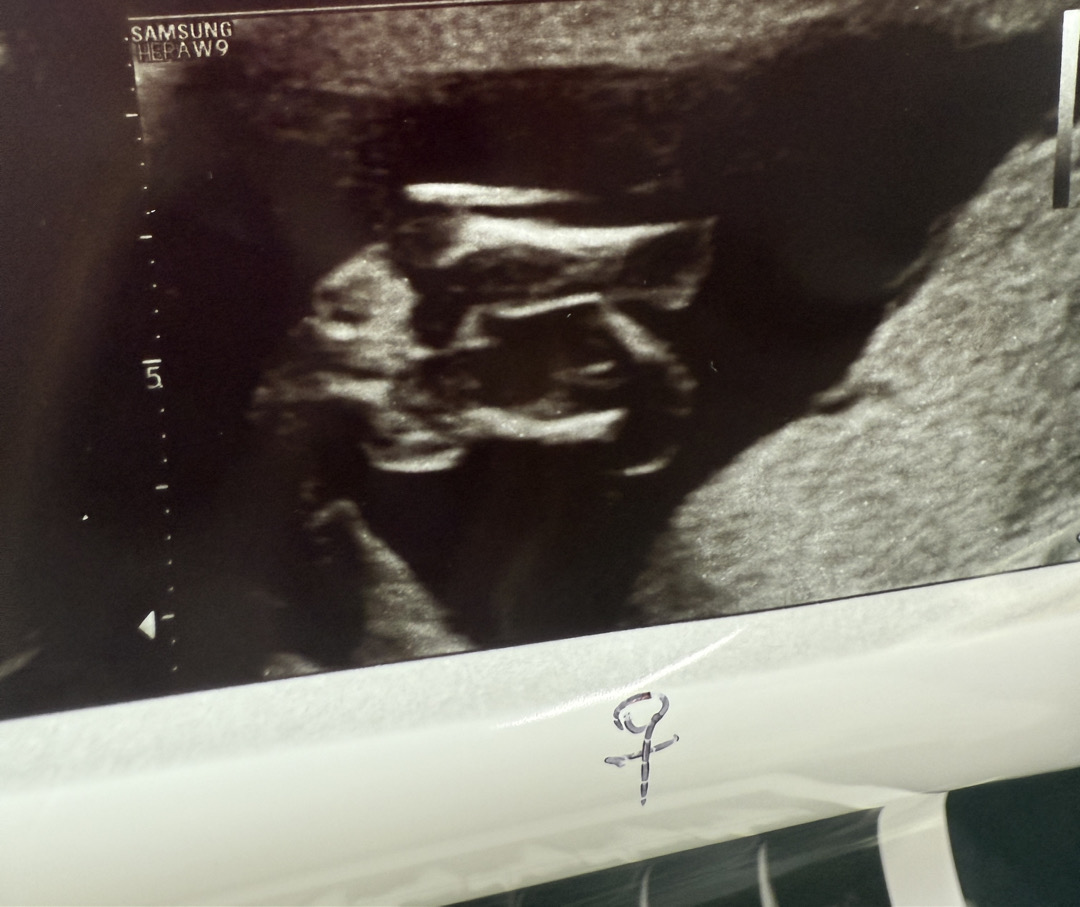

14주 성별 반전 있을까요?!

어제 성별맛집으로 유명한 서브병원에서 초음파 보고 왔습니다! 선생님께선 거의 딸 확정느낌으로 말씀해주셨는데 딸->아들 반전은 많다고해서 궁금한 마음에 올려봅니다ㅜㅜ 제눈엔 없는걸로 보이는데 이런경우에도 반전되는 경우가 종종 있나요?!

아들은 삼각점이 확실히 보여요. 사진속에서 점은 안 보이네요.